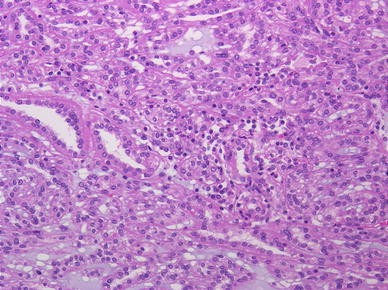

The tumor consisted of cuboidal and oval or spindle-shaped cells arranged in tubular and papillary patterns embedded in the myxoid stroma (H&E, reduced from ×200)